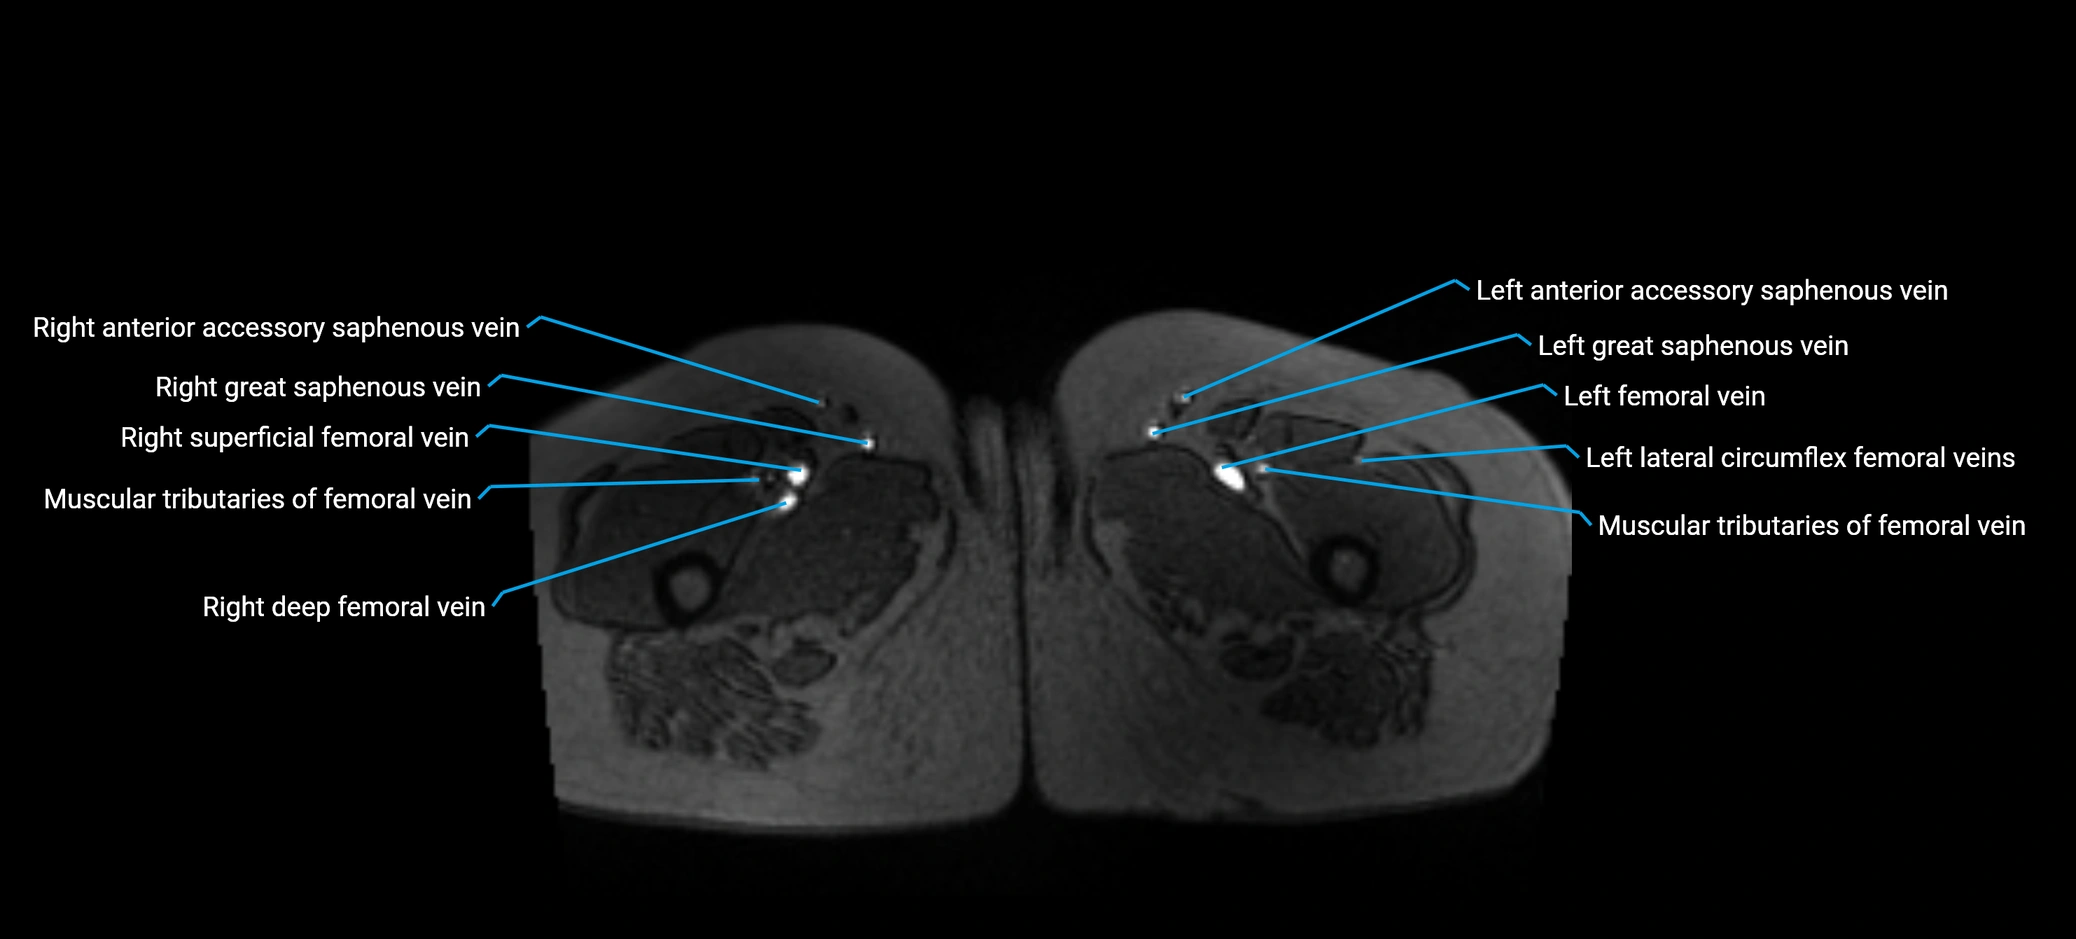

MRI image

image